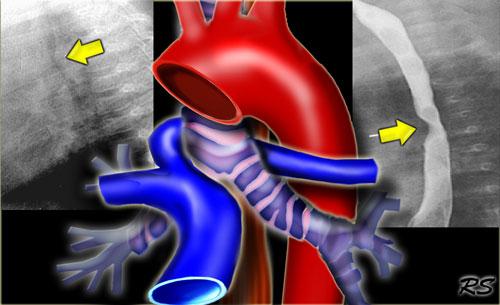

Quai động mạch chủ phải kèm động mạch dưới đòn trái bất thường

Quai động mạch chủ phải kèm động mạch dưới đòn trái bất thường thường là phát hiện tình cờ.

Tuy nhiên, quai động mạch chủ phải với phân nhánh đối xứng (mirror-image branching) hầu như luôn đi kèm với bệnh tim bẩm sinh.

CT cho thấy quai động mạch chủ phải (R) và động mạch dưới đòn trái bất thường (mũi tên) xuất phát thấp từ quai và chạy sang trái phía sau thực quản và khí quản.

Bên trái là hình chụp thực quản cản quang của bệnh nhân có quai động mạch chủ phải tạo ra ấn lõm phía sau trên hình chiếu nghiêng (mũi tên xanh dương).

Sơ đồ minh họa động mạch dưới đòn trái bất thường (L SCA) nằm phía sau khí quản và thực quản.

Quai động mạch chủ đôi – TRÁI: Quai phải và quai trái ấn lõm thực quản (mũi tên) ở các mức độ khác nhau – PHẢI: Hình chụp mạch máu với quai đôi ở bệnh nhân 65 tuổi không có triệu chứng

Quai động mạch chủ đôi (Double Arch)

Quai động mạch chủ đôi thường biểu hiện bằng tắc nghẽn đường thở, khó nuốt và hít sặc ở trẻ em.

Các quai ấn lõm thực quản ở các mức độ khác nhau.